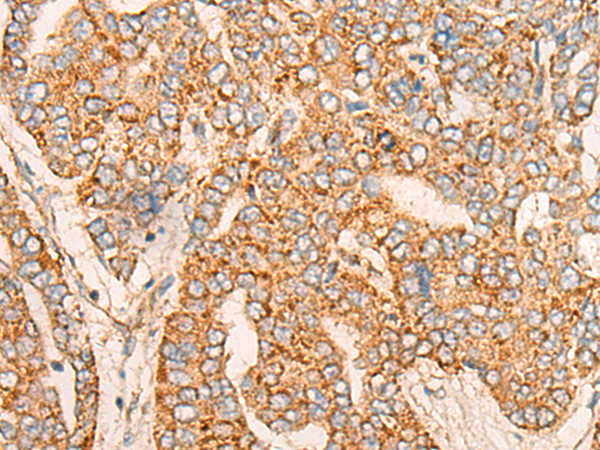

IHC positive control:

Human liver cancer

IHC Recommend dilution:

25-100